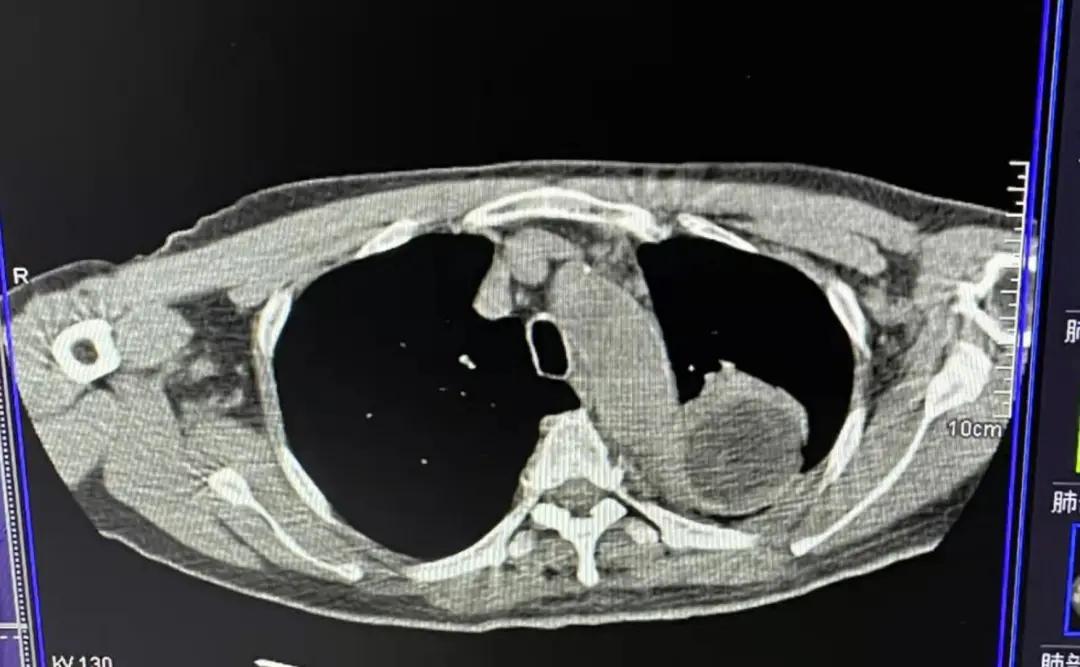

4月7日,重庆大学附属肿瘤医院中医肿瘤治疗中心顺利完成与北京中医药大学东方医院合作的国家重点研发计划项目——Ⅲb/Ⅳ非小细胞肺癌(NSCLC)绿色治疗方案的多中心随机对照临床研究第二例患者。该患者62岁,肺癌ⅥA期,经过冷冻消融技术治疗后冰球全部覆盖肿瘤,并且肿瘤已经出现局部坏死现象,治疗取得阶段性进展。